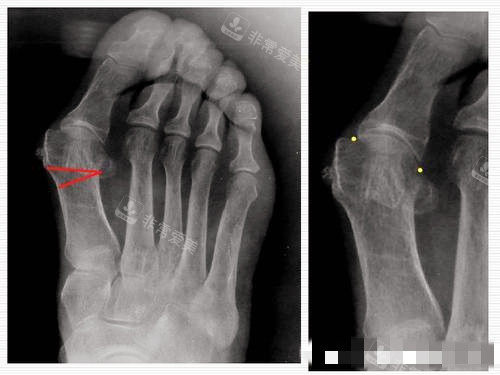

医生会对患者的脚部进行多方面的检查,包括X光片、CT等影像学检查,以较准了解大脚骨的程度、骨骼的结构和关节的情况。